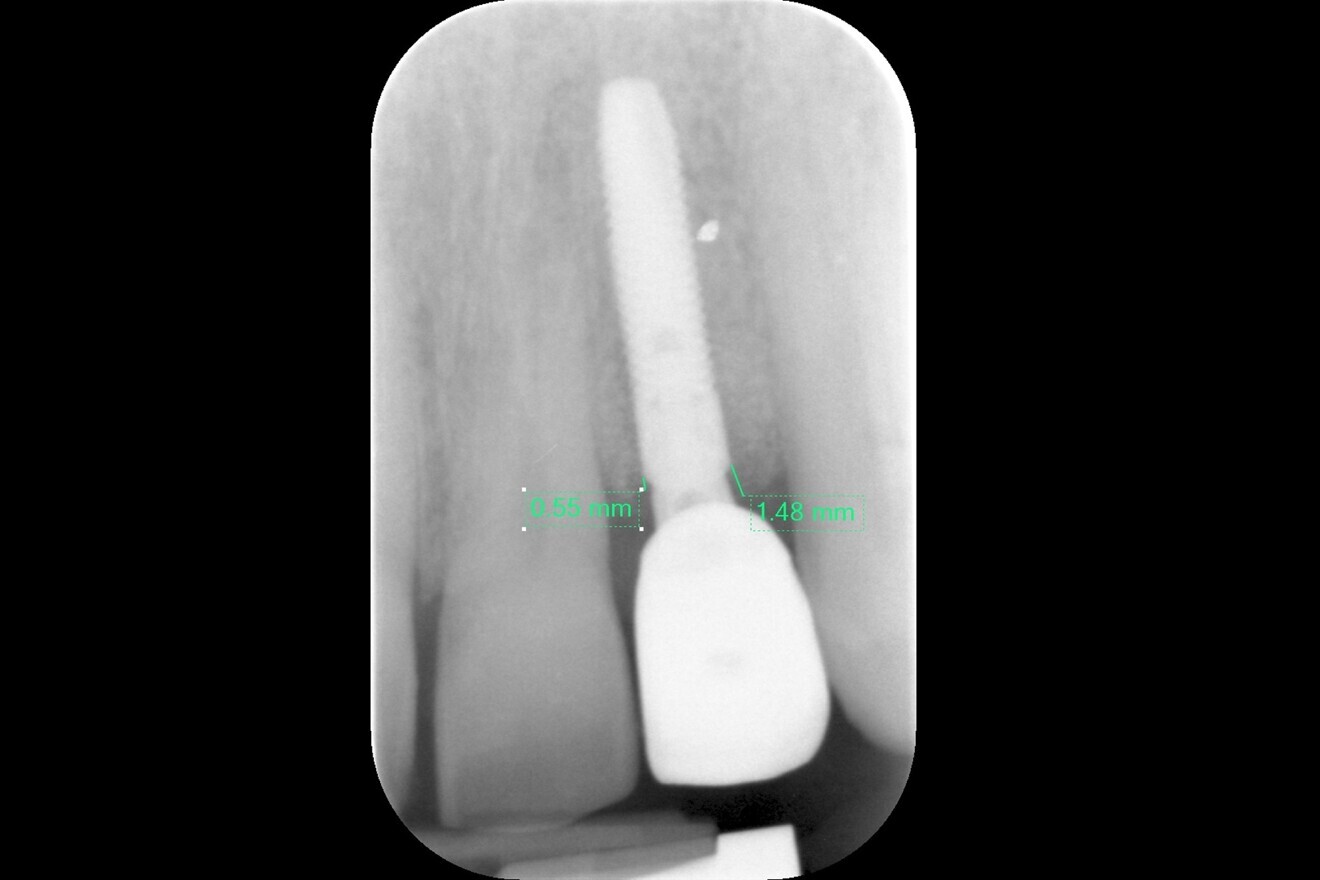

Tooth #11 was immobile and associated with adequate ridge width and a wide band of keratinised tissue (Fig. 1). There was also a favourable Class I incisor relationship and adequate space to accommodate an implant-supported restoration. A CBCT scan of the site revealed an inadequately endodontically treated tooth with a lack of an apical seal and incomplete obturation of the canal. The tooth benefited from good bone support provided by a robust facial bone plate at the alveolar crest (Fig. 2), but there was a large periapical dentigerous cyst measuring approximately 10 × 8 mm, extending to the mesial surface of tooth #12, and complete fenestration of the facial plate superiorly (Fig. 3). The prognosis of the tooth was deemed to be hopeless, and extraction was indicated.

Fig. 2: CBCT scan of failing tooth #11, showing inadequate root canal treatment and apical fenestration but an intact labial-crestal plate.